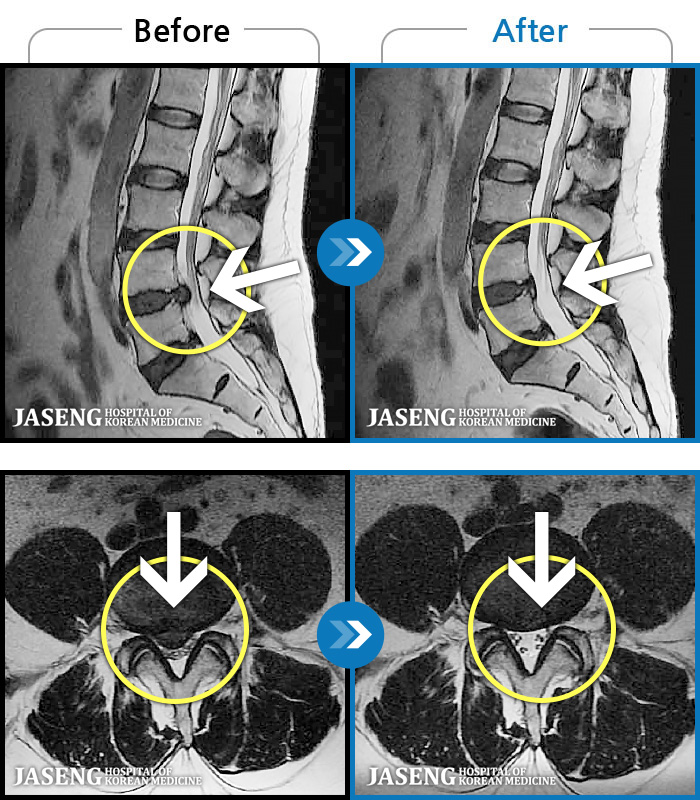

MRI ġ

119 MRI ũ ʸ Ȯϼ.

[Կñ:23.08.01~23.11.18]

[_㸮ũ] 㸮 ٸ ؼ ɰų

No.116

ȸ 732

2023.12.08